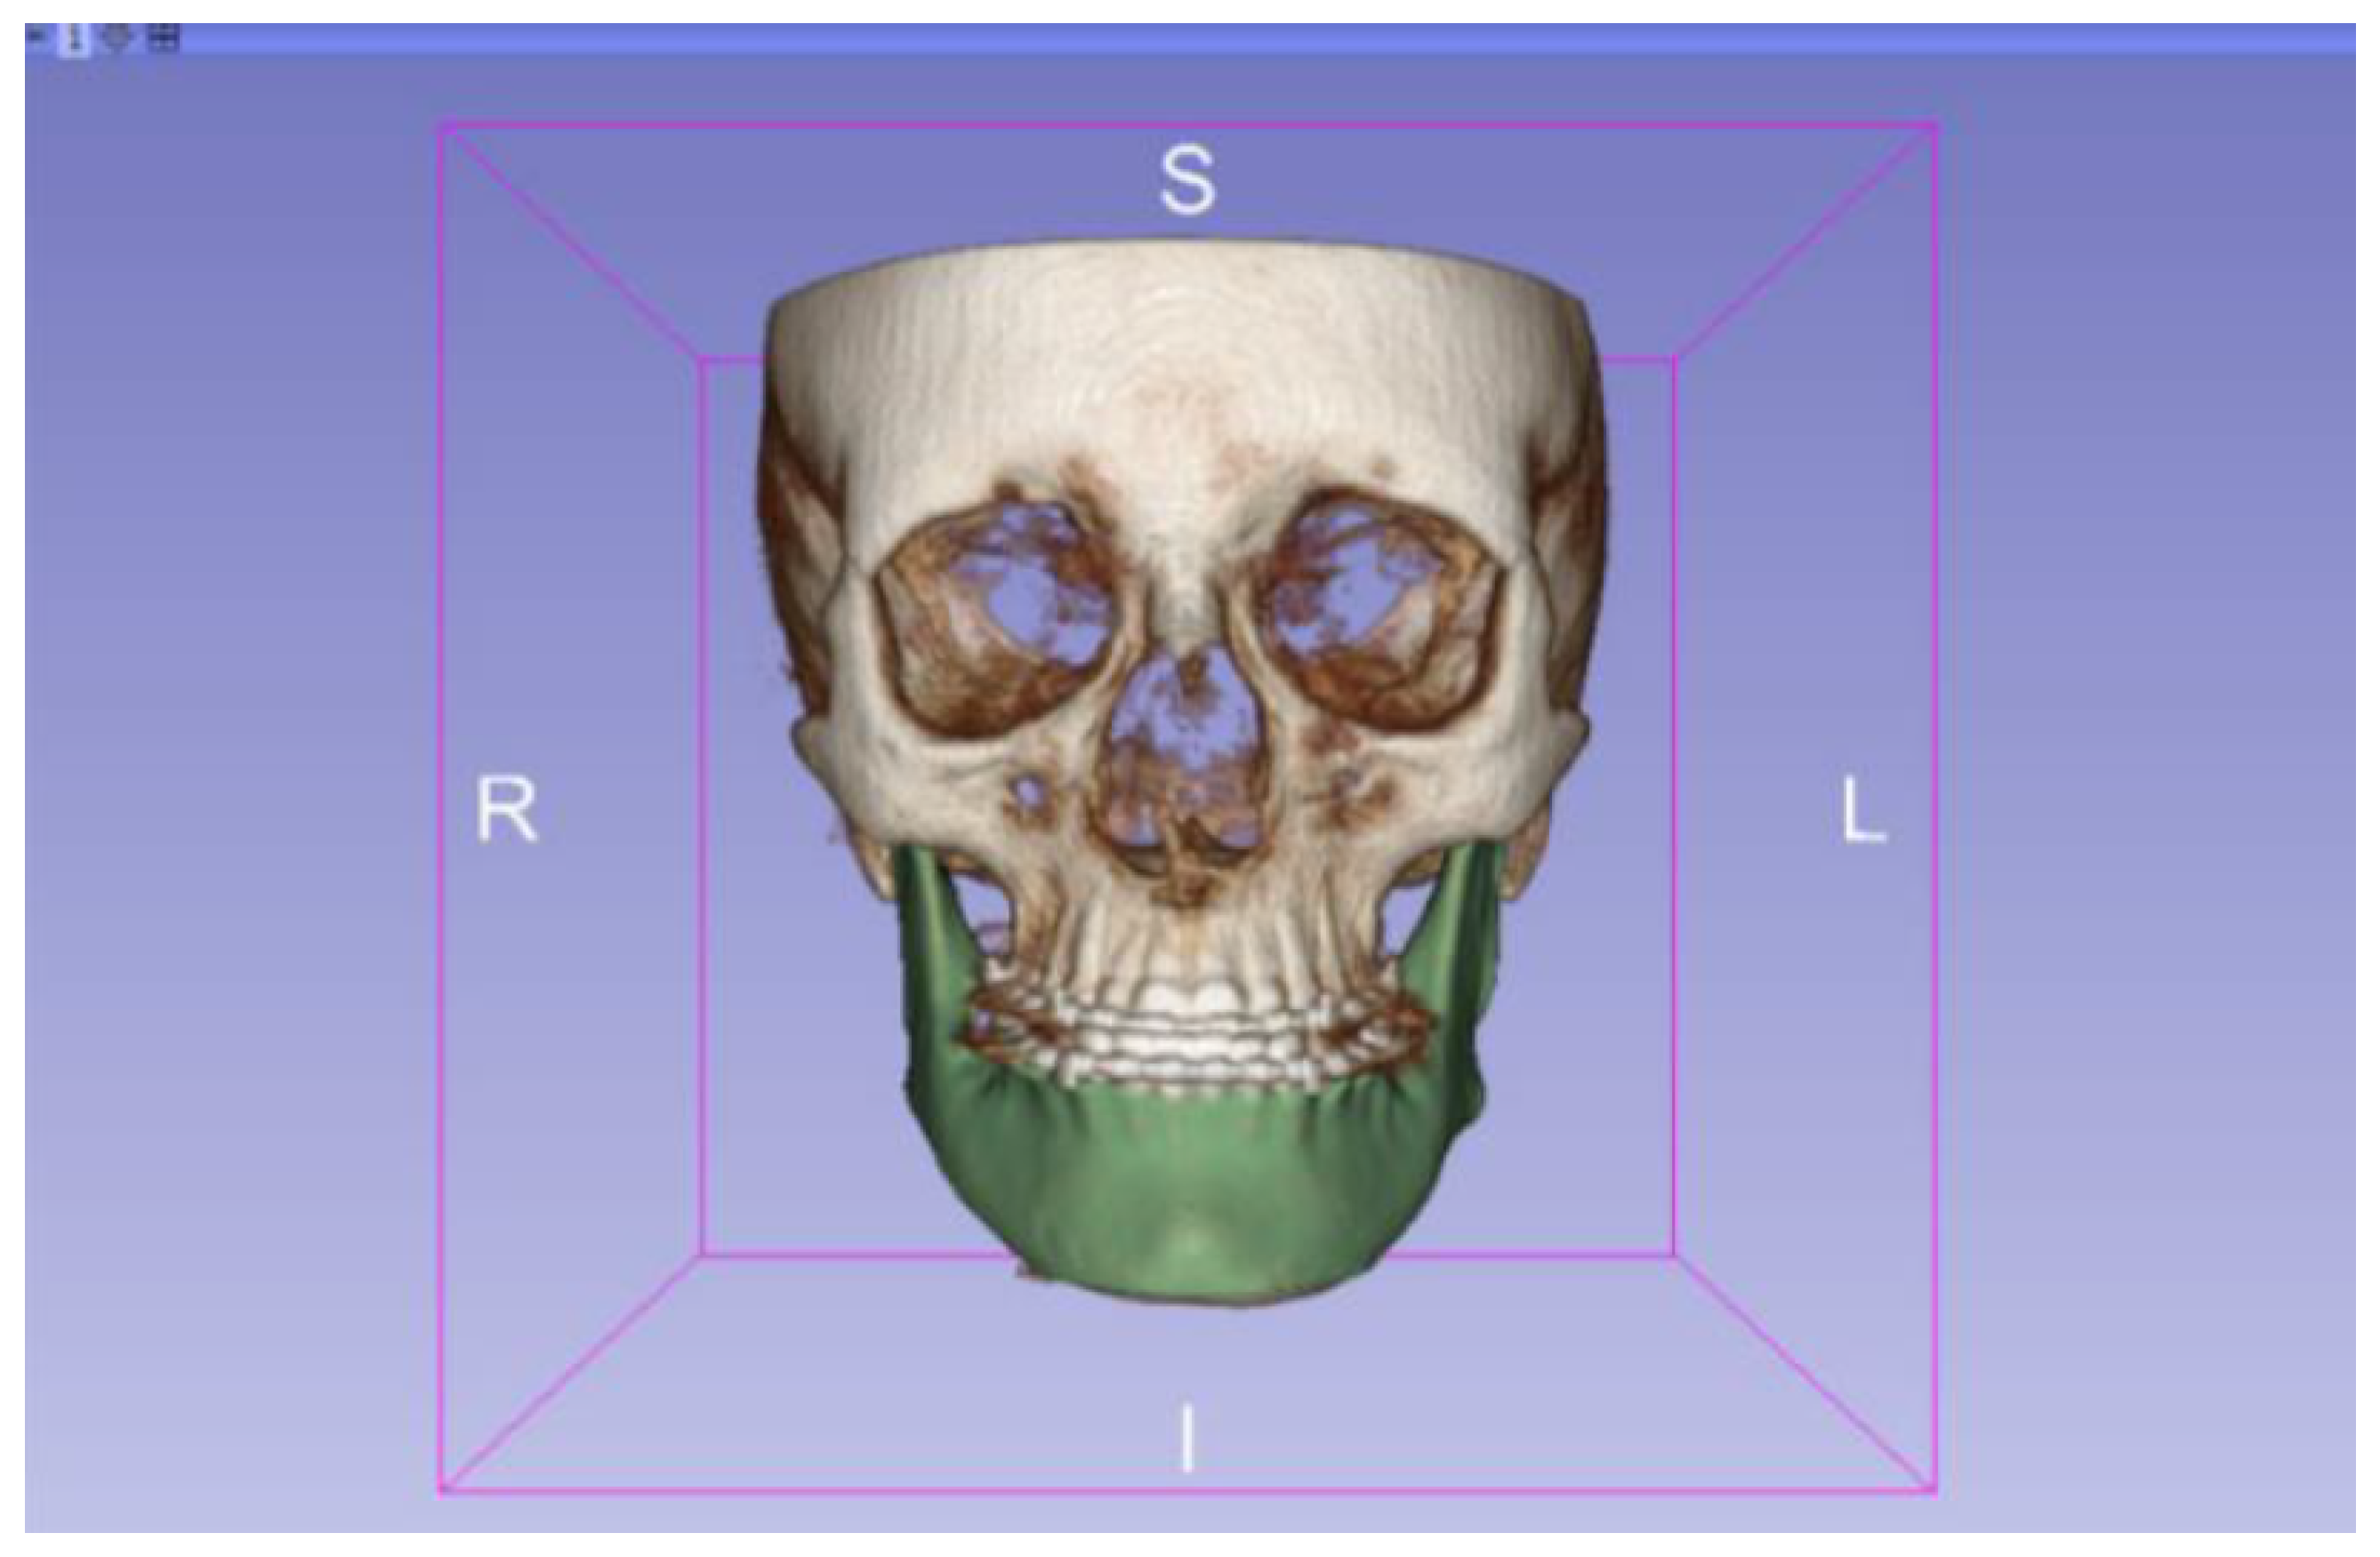

3.2. Human Lower Jaw

3.2.1. DICOM-to-STL Files